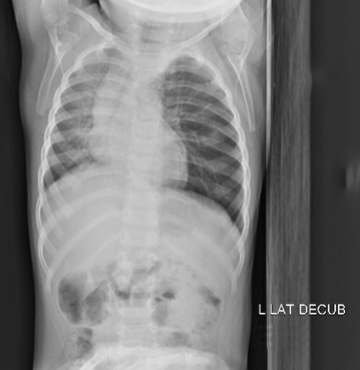

Answer: Non-radiopaque foreign body in left airway beyond the carina with hyper lucency of the left lung consistent with air trapping

- Air trapping seen on all views

- normally with decubitus xrays dependent lung collapses slightly, which is seen here on the right but not on the left

- patient taken to the OR with ENT and peanut was removed via bronchoscope from the left main stem bronchus, she was discharged the following day